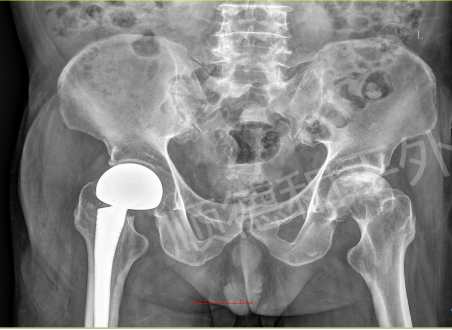

事发当天下午,陈阿姨(化名)在家中不慎摔倒,右侧臀部重重着地,瞬间传来剧烈疼痛,无法站立行走。家人紧急将其送往附近医院检查,X线片提示“右股骨颈骨折(GardenIV型)”,这是股骨颈骨折中较为严重的类型,保守治疗效果差,且极易导致股骨头坏死等后遗症。为寻求更优质的治疗方案,陈阿姨在家人的陪同下转至顺德和平外科医院急诊。

我院急诊医生接诊后,迅速完善相关检查。专科查体显示,陈阿姨右髋关节轻度肿胀,局部压痛及纵向叩击痛明显,髋关节活动严重受限,患肢较健侧短缩2cm,万幸的是远端各趾血运、感觉及活动正常。结合外院影像学资料,“右股骨颈骨折”诊断明确。更棘手的是,陈阿姨年事已高,基础疾病较多,这无疑增加了治疗的复杂性和手术风险。

手术当日,副主任俞泉带领团队凭借丰富的临床经验和精湛的微创技术,有条不紊地开展人工股骨头置换手术。术中严格遵循精准操作原则,避开重要血管神经,优化手术流程,整个手术仅用1小时便顺利完成,出血量少,患者生命体征始终保持平稳。